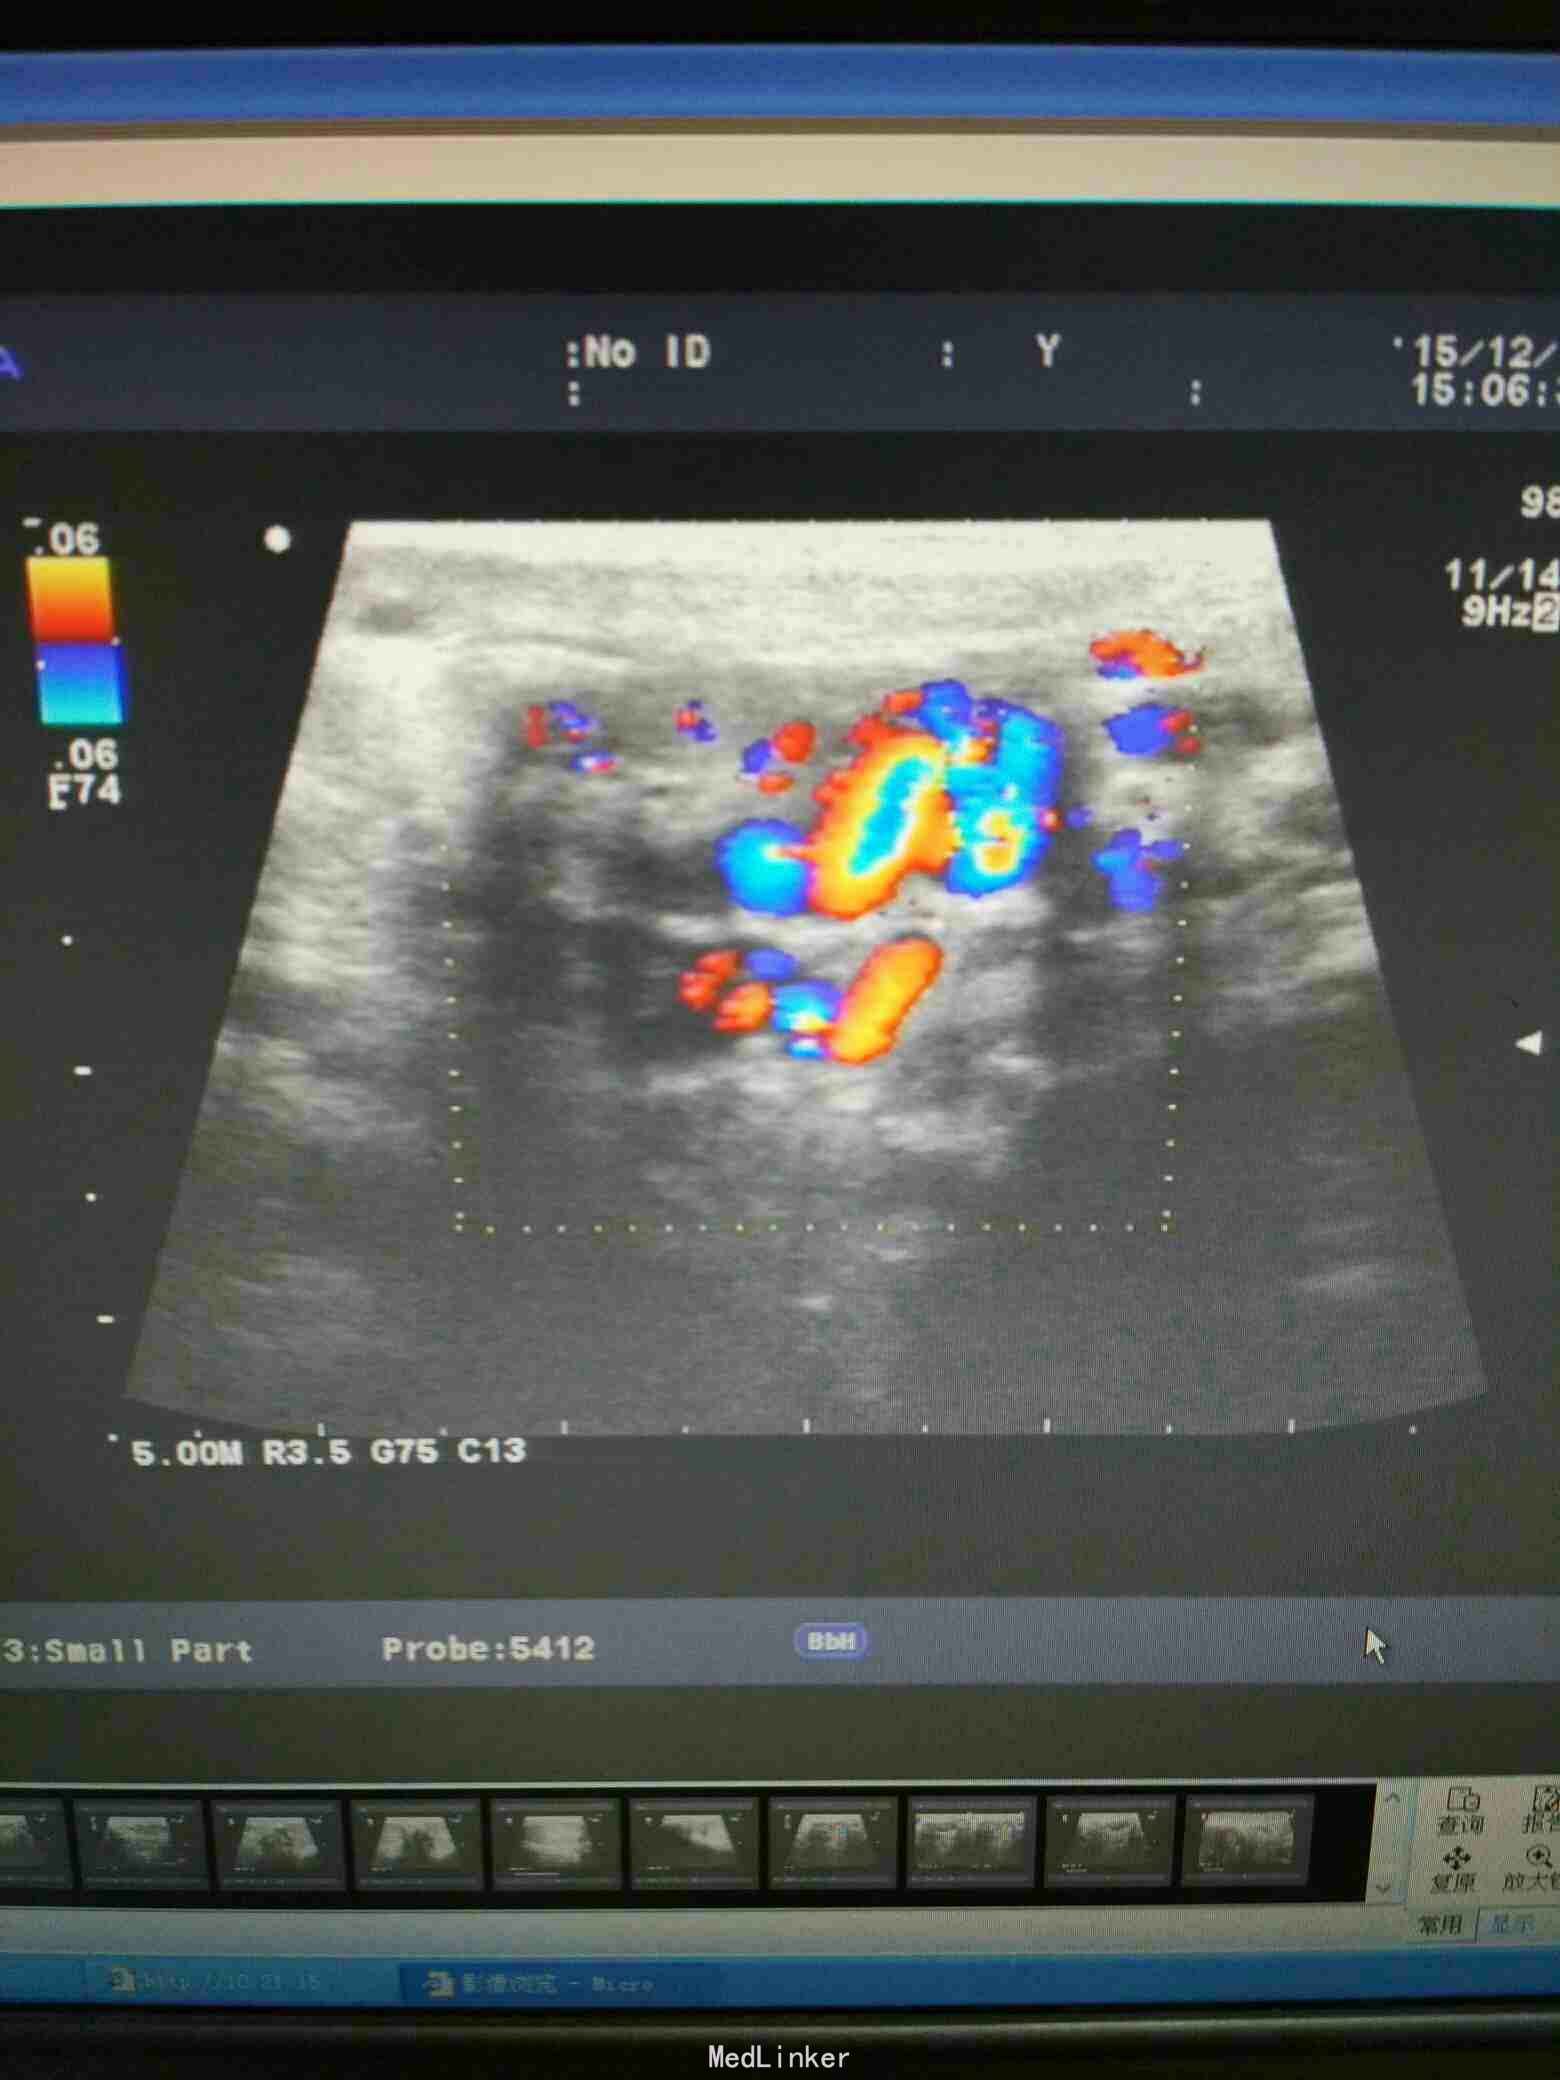

左侧精索静脉曲张,右侧附睾肿物,大小约2cm*1.8cm,质地韧,光滑。

B超:右侧附睾囊肿,左侧精索静脉曲张

腰硬联合麻醉下左侧显微镜下精索静脉结扎、右侧精囊镜下钬激光囊肿切除术。